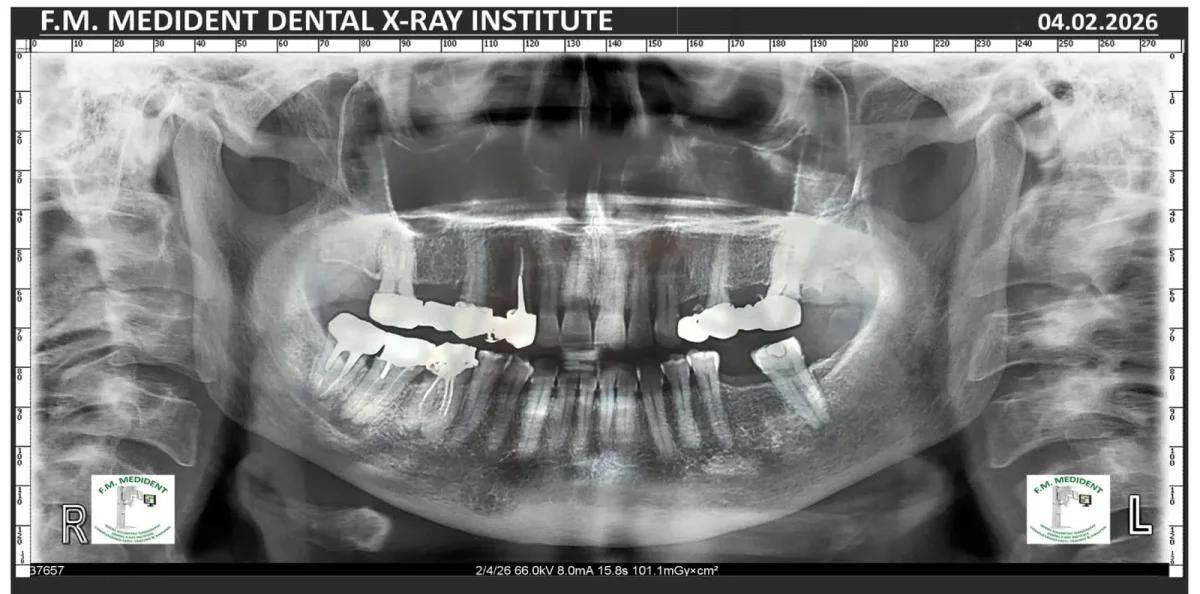

Cazuri reale înainte și după, din tratamente realizate în clinică.

Înainte

DupăExemple reale din cazuri tratate în clinică.